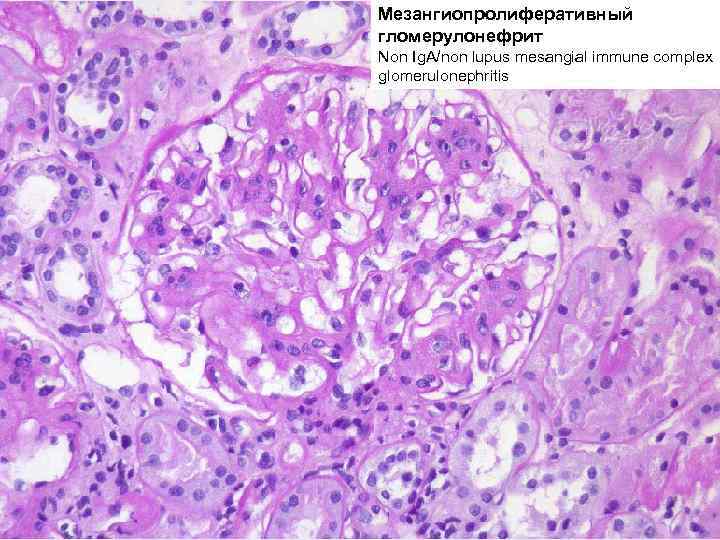

Механизм остро го диффузного гломерулонефрита